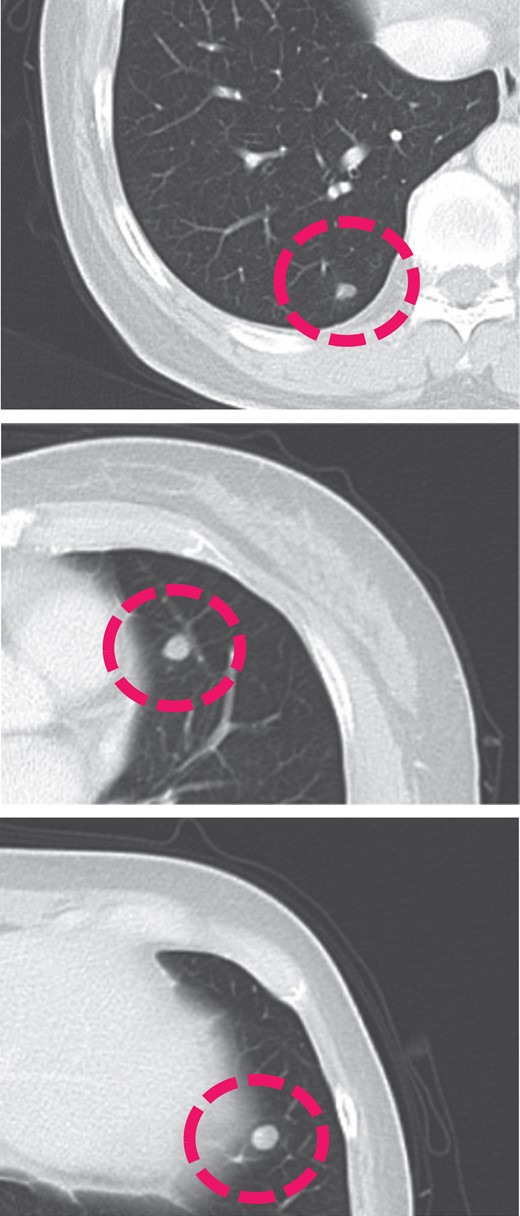

A 50-year-old woman, Gravida 3, Para 1, presented to our department with irregular genital bleeding for 2 months. Her last menstrual period had been 2 months before. Her obstetrical history included a normal vaginal delivery 13 years before and two spontaneous abortions 8 and 11 years previously. Transvaginal ultrasonography showed an enlarged uterus with endometrial thickening with an echogenic pattern (Fig. 1). As endometrial cancer was suspected first, an endometrial biopsy and magnetic resonance imaging (MRI) were performed. The endometrial biopsy revealed decidual tissues, and the MRI revealed invasion of a uterine corpus tumor into the myometrium (Fig. 2). A week later, the patient admitted to the hospital with continuation of irregular vaginal bleeding. Second endometrial biopsy was done and serum β-human chorionic gonadotropin (hCG) level was also measured owing to suspicion of a hydatidiform mole. The serum hCG level was over 225 000 mIU/mL, and the endometrial biopsy revealed a complete hydatidiform mole. Because the patient's hemoglobin level was 7.0 g/dL, owing to the continuation of uterine bleeding, we transfused 800 mL of red cell concentrate and discharged the patient. A lung metastasis, 1 cm in diameter, was observed on a contrast computer tomography scan (Fig. 3), and an invasive mole with lung metastasis was diagnosed. Because the patient did not desire preservation of her uterus or adnexa, we offered her a total abdominal hysterectomy (TAH) and bilateral salpingo-oophorectomy (BSO). At her next consultation for the continuous genital bleeding, a tumor of the right labium minus was recognized and histologically confirmed as a metastatic lesion of the mole (Fig. 4). The patient underwent TAH and BSO. Unfortunately, a tumor of right labium minus had spontaneously fallen off during surgery. In a gross specimen, molar vesicles were recognized at the uterine corpus with the right ovary a little swollen (Fig. 5). The invasions into myometrium by both villi and the trophoblasts were histopathologically confirmed (Fig. 6). In addition to the labium minus tumor, a metastatic lesion of the right ovary was diagnosed. The final pathological diagnosis was metastatic invasive hydatidiform mole, Stage III. The patient's serum hCG level fell to 10 779 mIU/mL after her operation. The patient was then started on administered methotrexate 20 mg/body intramuscularly, 5 days a week at 2 weeks intervals. Serum hCG levels are measured for the estimation of chemotherapy [4]. Her serum hCG level rapidly fell to 1.2 mIU/mL after four courses of methotrexate (Fig. 7). Two additional courses of methotrexate were completed, and there has been no evidence of recurrent disease for 6 months.

Contrast computed tomography scan showing the metastasis in the lungs.